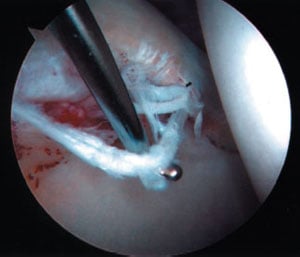

Removal of loose body from inside the hip

Through the second opening (portal) instruments are inserted to shave tissue, cauterize structures, or remove pieces. On occasion, holes may be drilled into patches of bare bone where the cartilage has been lost. This technique, called "microfracture" or "picking" incites localized bleeding and encourages the formation of fibrocartilage (repair cartilage). Saline is pumped through the joint during the procedure to improve visualization and flush out debrided tissue.